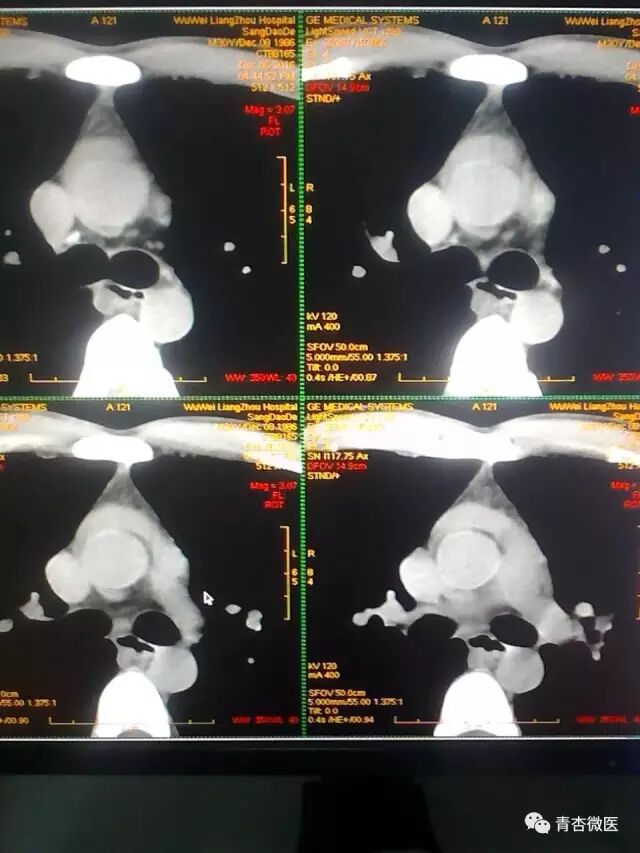

李晓副院长示开启无障碍绿色通道,优先为重伤患者行全面CT检查,在李琴护士长紧张有序的安排下,陆兴华、刘静、严华、张霞护师全程陪检。影像中心庞永亮主治医师、原桂梅主治医师早已做好准备,以最快的速度完成CT检查。其中1名30岁男性患者影像学报告:心包积液,纵膈积液。急救中心全体值班人员表情凝重,压力陡增。

编者语:急性心包填塞是外伤性心脏破裂或心包内血管损伤造成心包腔内血液积存的危急重症,也称为血心包或心包填塞,是心脏创伤的急速致死原因。由于心包的弹力有限,急性心包积血达150ml即可限制血液回心和心脏跳动,引起急性循环衰竭,进而导致心跳骤停,必须采取积极措施进行抢救。争分抢秒,边抢救,边诊断,边治疗。对于不必要的检查,尽量避免,切勿为明确诊断而延误抢救治疗。